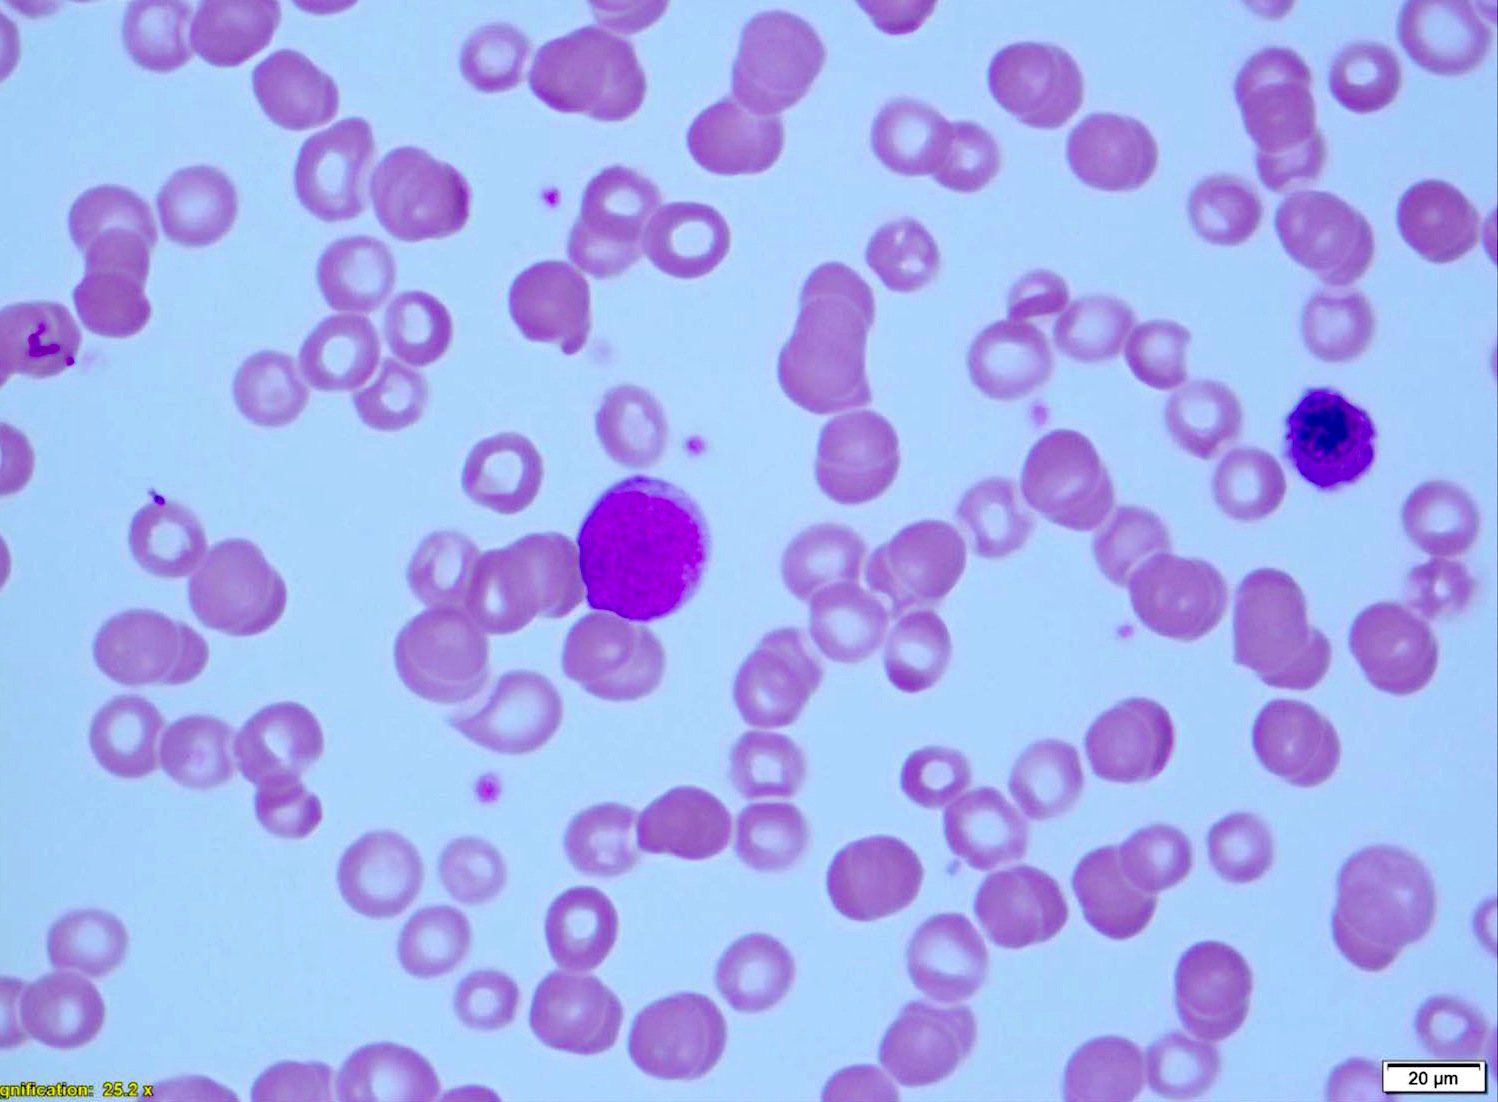

Peripheral smear description

- Prolymphocytoid-like morphology (leukemic form of mantle cell lymphoma)

- Patients present with high leukocyte count (often > 100 x 109/L)

- Extensive bone marrow involvement

- Prominent nucleoli in circulating cells in blood

- Intermediate to large sized cells

- A single, prominent pink nucleolus

- Prominent splenomegaly

- A subset are pleomorphic mantle cell lymphomas (Am J Clin Pathol 2001;115:571, Leuk Lymphoma 2001;41:683, Am J Clin Pathol 2002;117:246)

- Blastoid morphology (leukemic form of blastoid mantle cell lymphoma)

- High leukocyte count

- Extensive bone marrow involvement

- Blastoid morphology

- Complex karyotypes

- 8q24 anomalies and MYC rearrangements (Mod Pathol 2002;15:1266, Br J Haematol 2001;115:66)